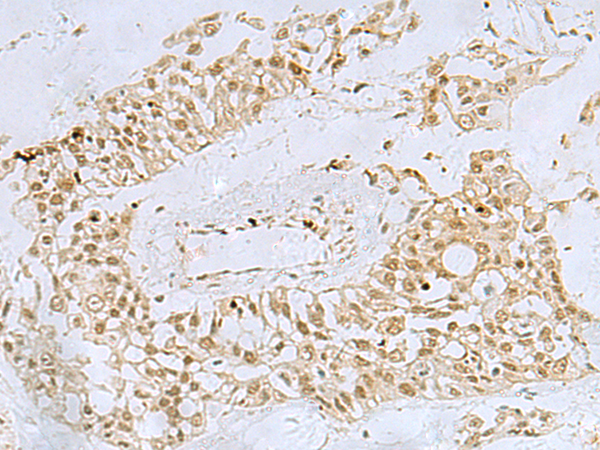

The image is immunohistochemistry of paraffin-embedded Human colorectal cancer tissue using P13426(FOXQ1 Antibody) at dilution 1/30. (Original magnification: ×200) |